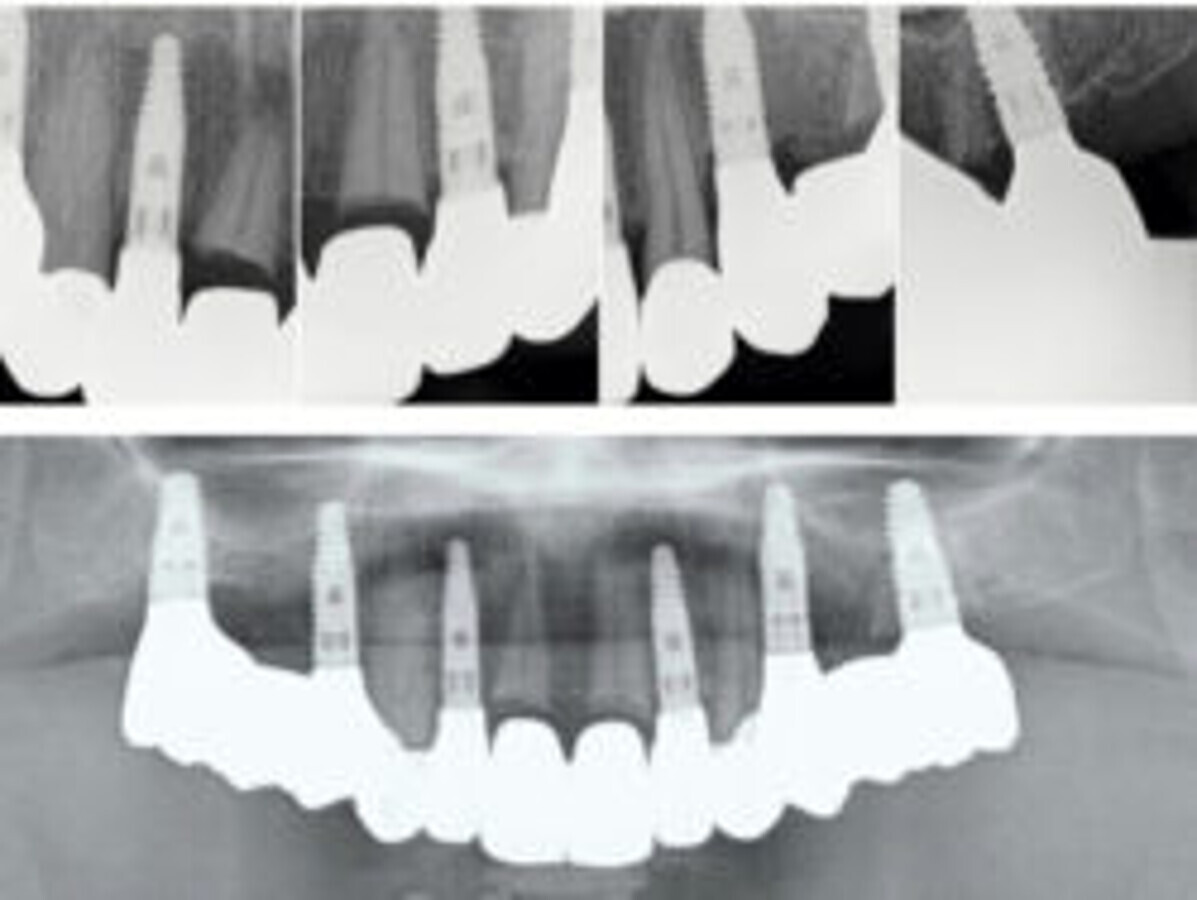

Slika 21. Rendgenska slika nakon dvogodišnjeg praćenja. Na području zadržanih/očuvanih korijena ne može se vidjeti gubitak krestalne kosti oko implantata niti znakovi periapikalnog parodontitisa.

Definitivni protetski rad napravljen je nakon što je završila faza oseointegracije implantata s tri monolitna mosta od cirkonijevog dioksida (DD CubeX, Dental Direkt) proizvedenih CAD/CAM postupkom. Mostovi su pomoću vijaka pričvršćeni na titanske abutmente (PS TiB, BEGO Implant Systems) (Slike 14–16). Pravilan dosjed protetske nadogradnja se nakon umetanja potvrdio rendgenskom snimkom (Slika 17.). Kontrolni pregled nakon dvije godine u srpnju 2019. pokazao je izvrsno estetsko i kliničko stanje mekog tkiva (Slike 18–20). U području implantata radiografski se nije mogao utvrditi gubitak krestalne kosti (Slika 21.). Oba korijena središnjih sjekutića koji su ostavljeni u alveoli kao ni distobukalni korijen zuba 26 nisu pokazali nikakve znakove periapikalne upale. Pacijentica nije imala nikakvih pritužbi, a oralna higijena značajno se poboljšala tijekom razdoblja praćenja.